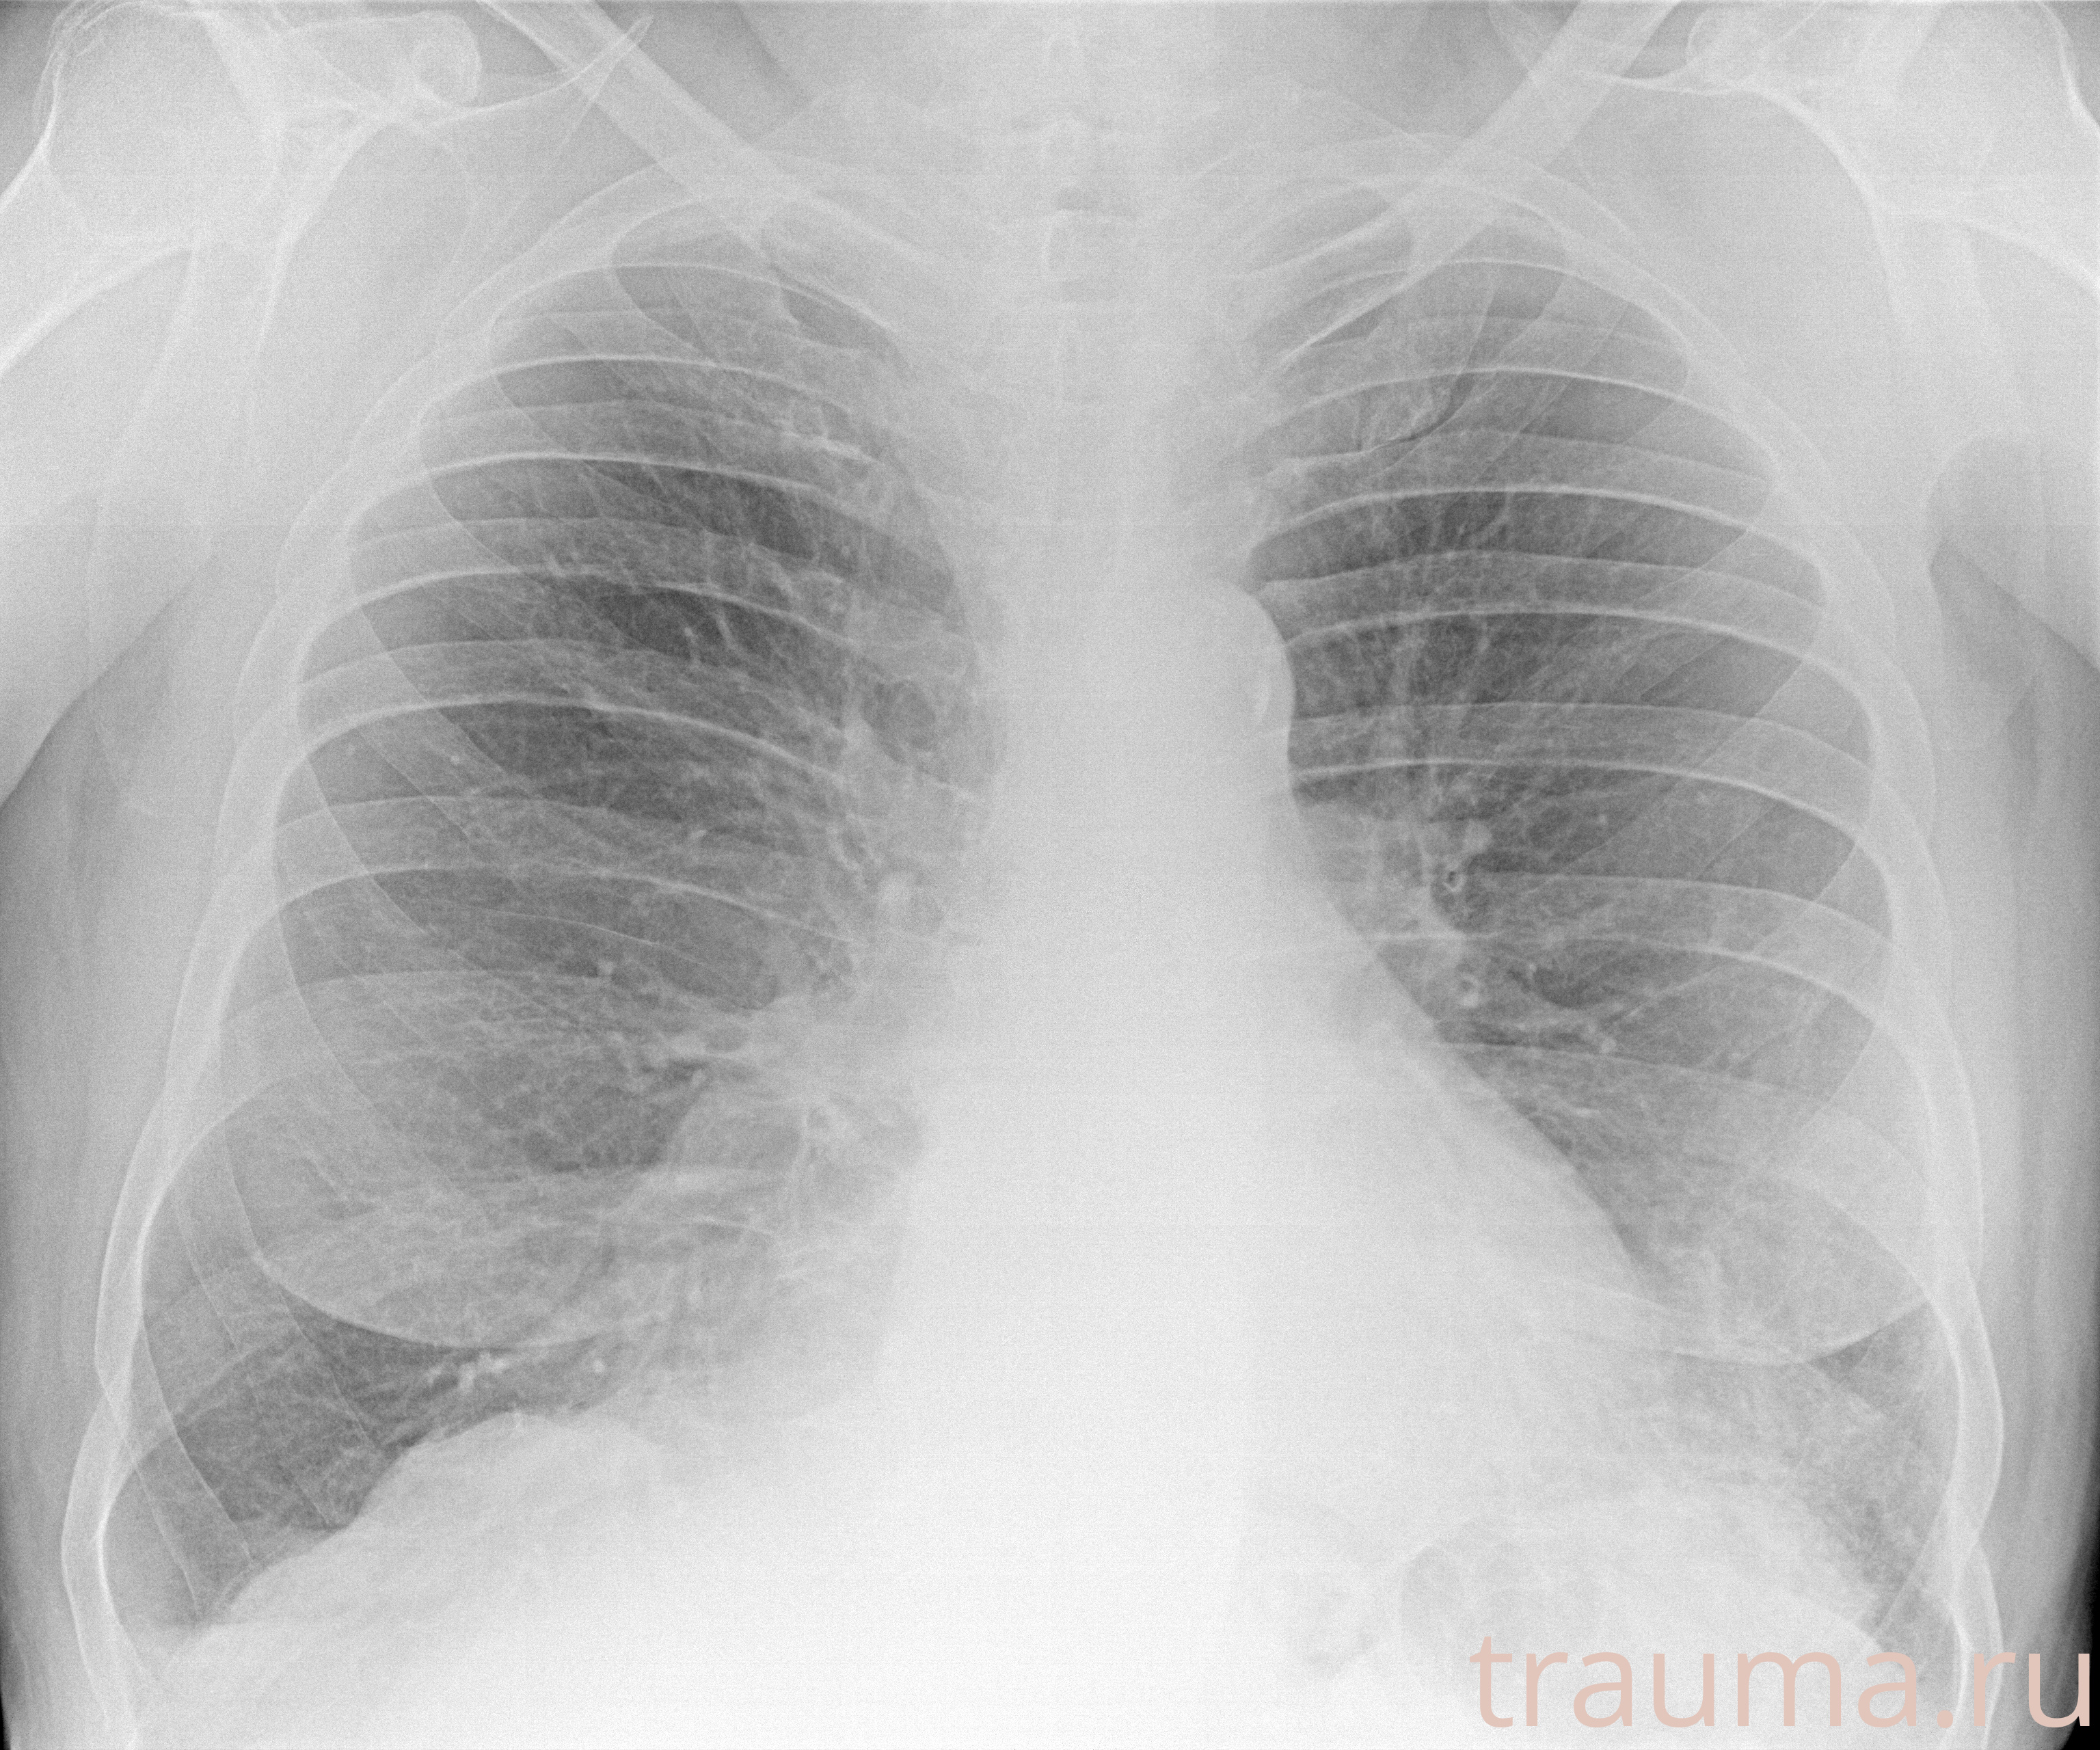

Рентген на дому: по вашему адресу приезжает врач-рентгенолог, травматолог-ортопед с мобильным рентгеновским аппаратом, проводит диагностику травмы или заболевания, делает необходимые рентгенограммы, дает рекомендации по дальнейшему лечению. Получить качественные снимки в домашних условиях возможно благодаря уникальной методике, разработанной МосРентген Центром для института  Склифосовского

при переломе шейки бедра и пневмонии от компании МосРентген Центр - партнера Института имени Склифосовского